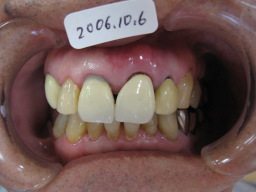

| インプラント(人工歯根)を植えた所に 仮歯(テック)を作り、手術の終わりです。 骨が固まるまで数ヶ月待ち、それから、 はずした歯(補綴物)が入ればそれを 入れます。 歯の周りにあるのは、ゴムで、血(血餅)が流れ 出ないようにしています。こうする事によって、 きれいな歯ぐきが再生されます。 |

インプラント(人工歯根)をする事によって、 隣の歯を削らないで済むので、歯を傷めません。 むし歯は歯を削った境目から出来やすいので、 インプラントは、これも防ぐ事が出来ます。 |